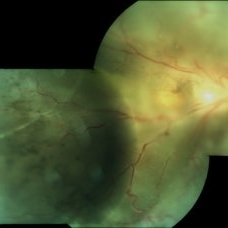

Familial Exudative Vitreoretinopathy

Fundus Photograph of 25-year-old lady with Familial Exudative Vitreoretinopathy : Left eye showing pale optic disc with disc drag and sheathing of vessels.

Photographer: Miss Ashwini Borde

Imaging device: Carl Zeiss 450 plus IR

Condition/keywords: familial exudative vitreoretinopathy (FEVR)